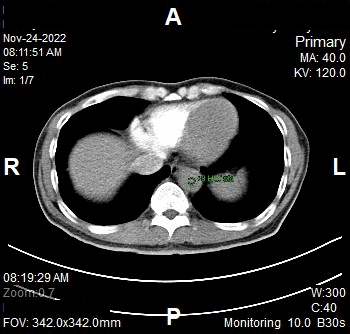

Cortico-Medulary Phase

- Plan the Scan FOV (SFOV) box at topogram image.

- Set the top and bottom line to cover entire renal..

- Ensure the lateral line to cover patient’s body outline.

- Remind the patient before scanning as the breathing instruction will be given.

- Delay after triggering: 10 seconds (to enhancement of kidney outer cortex).

Reconstruction of Cortico-Medulary Phase